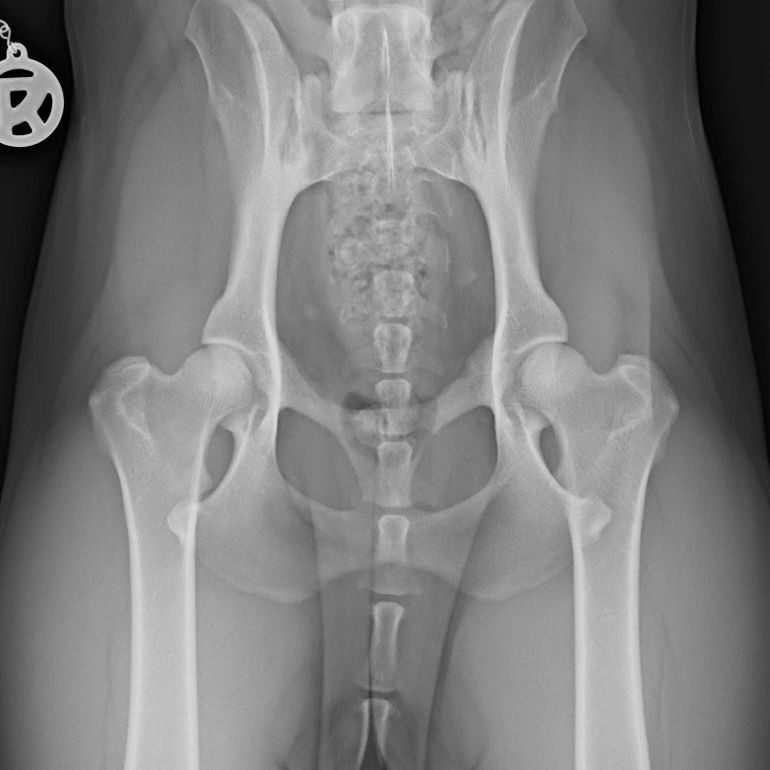

Die Hüftgelenksdysplasie (HD) ist eine multifaktorielle Erkrankung, die häufig bei Haushunden vorkommt und eine Fehlentwicklung des Hüftgelenks zur Folge hat. Neben der haltungs- und ernährungsbedingten Komponente, trägt vor allem auch eine genetische Komponente zu ihrer Entstehung bei. Besonders betroffen sind größere Hunderassen wie z.B. Deutschen Schäferhunden Golden Retrievern Labrador Retrievern Boxer oder Berner Sennenhunde Es können jedoch auch kleine Hunde von einer Hüftgelenksdysplasie betroffen sein. Entgegen der landläufigen Meinung eine HD könnte erst im Alter von 12 Monaten zuverlässig diagnostiziert werden, kann man Veränderungen im Hüftgelenk schon ab einem Alter von 16 Wochen über ein spezielles röntgendiagnostisches Verfahren (PennHIP) zuverlässig feststellen. Gerade bei Hündinnen, die später zur Zucht zugelassen werden sollen, wäre dies Verfahren anzuraten, da dieses genauere Aussagen über die Gesundheit der Hüfte zulässt, als das herkömmliche Röntgenverfahren. Die HD gehört zu den degenerativen Erkrankungen, sie schreitet mit dem älter werden des Hundes immer weiter voran. Die Symptome können von Hund zu Hund unterschiedlich sein und variieren je nach Schweregrad der Erkrankung. Einige der häufigsten Symptome sind: Lahmheit oder Hinken: Der betroffene Hund kann Schwierigkeiten beim Laufen oder Stehen haben und ein Bein mehr belasten als das andere. Schmerzen: Hunde mit HD können Schmerzen oder Unbehagen in der Hüftregion zeigen, besonders nach körperlicher Aktivität oder bei kaltem Wetter. Steifheit: Betroffene Hunde können steif wirken, insbesondere nach dem Aufstehen oder nach dem Ruhen. Eingeschränkte Beweglichkeit: Hunde mit HD können Schwierigkeiten haben, ihre Beine vollständig zu strecken oder anzuheben, was zu einer eingeschränkten Beweglichkeit führt. Muskelschwund: Bei Hunden mit HD kann es zu einem Abbau der Muskulatur in den Hinterbeinen kommen, was zu einer verminderten Muskelmasse führt. Schwierigkeiten beim Aufstehen oder Hinlegen: Hunde mit HD können Schwierigkeiten haben, sich hinzulegen oder aufzustehen, und können dabei Schmerzen oder Unbehagen zeigen. Veränderungen im Gang: Der Gang des Hundes kann sich verändern, und er kann einen "hoppelnden" oder "schaukelnden" Gang entwickeln. Unwilligkeit, sich zu bewegen oder zu springen: Hunde mit HD können weniger aktiv sein und können es vermeiden, zu springen, zu rennen, Treppen zu steigen oder ins Auto zu springen. Ob und welche Symptome der Hund zeigt, ist tatsächlich von Patient zu Patient unterschiedlich - es gibt Hunde die mit einem leichten Befund ausgeprägte Schmerzanzeichen zeigen, genauso wie es Patienten mit einem schweren Befund gibt, die erst im Alter anfangen Symptome zu zeigen. Die Behandlung der Hüftgelenksdysplasie ist vielfältig, hier einige Beispiele: sollte der Hund übergewichtig sein, so empfiehlt sich als erstes eine Gewichtsreduktion. gezielter Muskelaufbau und eine damit einhergehende Stabilisierung des Gelenks haben einen hohen Mehrwert für den Hund - dies kann besonders gelenkschonend auf dem Unterwasserlaufband erfolgen, aber auch auf dem täglichen Spaziergang kann man Übungen einbauen, welche dabei helfen die Muskulatur aufzubauen. übermäßige Belastung des Gelenks sollte vermieden werden - Start-Stop-Spiele, wie z.B. das Ballspielen, sollten vermieden und lieber durch gelenkschonende Spiele (z.B. Dummysuche) ersetzt werden. der Rücken des Hundes sollte außerdem immer schön warm und trocken gehalten werden. Ein Hundemantel wird zum Teil zwar immer noch belächelt, bei einem Hund mit HD und nass-kaltem Wetter ist dieser jedoch eine große Hilfe. der Schlafplatz des Hundes sollte geschützt stehen und möglichst weich gepolstert sein. Eine Alternative ist das orthopädische Hundebett auch der Einsatz von Schmerzmitteln sollte nicht außer Acht gelassen werden - kein Hund sollte unnötigerweise unter Schmerzen leiden. Wenn der Hund Schmerzen hat, dann ist eine Beratung beim Tierarzt und eine Gabe von Schmerzmitteln angezeigt. Ich arbeite gerne mit Schmerzmitteln in der ersten Phase der Physiotherapie, damit wir schmerzfrei Muskulatur aufbauen und die nötigen Behandlungen durchführen können.